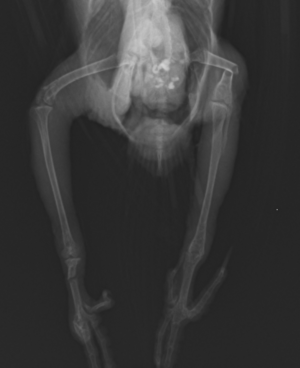

コザクラインコの両脚骨折

脚から出血し起立不能となったコザクラインコさんが来院されました。右の趾は1本欠損しており、またレントゲン検査にて右の足根中足骨及び左の大腿骨が折れていることが確認されました。

特に大腿骨は変位が酷く、このままでは自力での歩行は難しいと考えられました。

よって、全身麻酔をかけ、骨の中にピンを入れて固定を行う手術(ピンニング術)を実施しました。